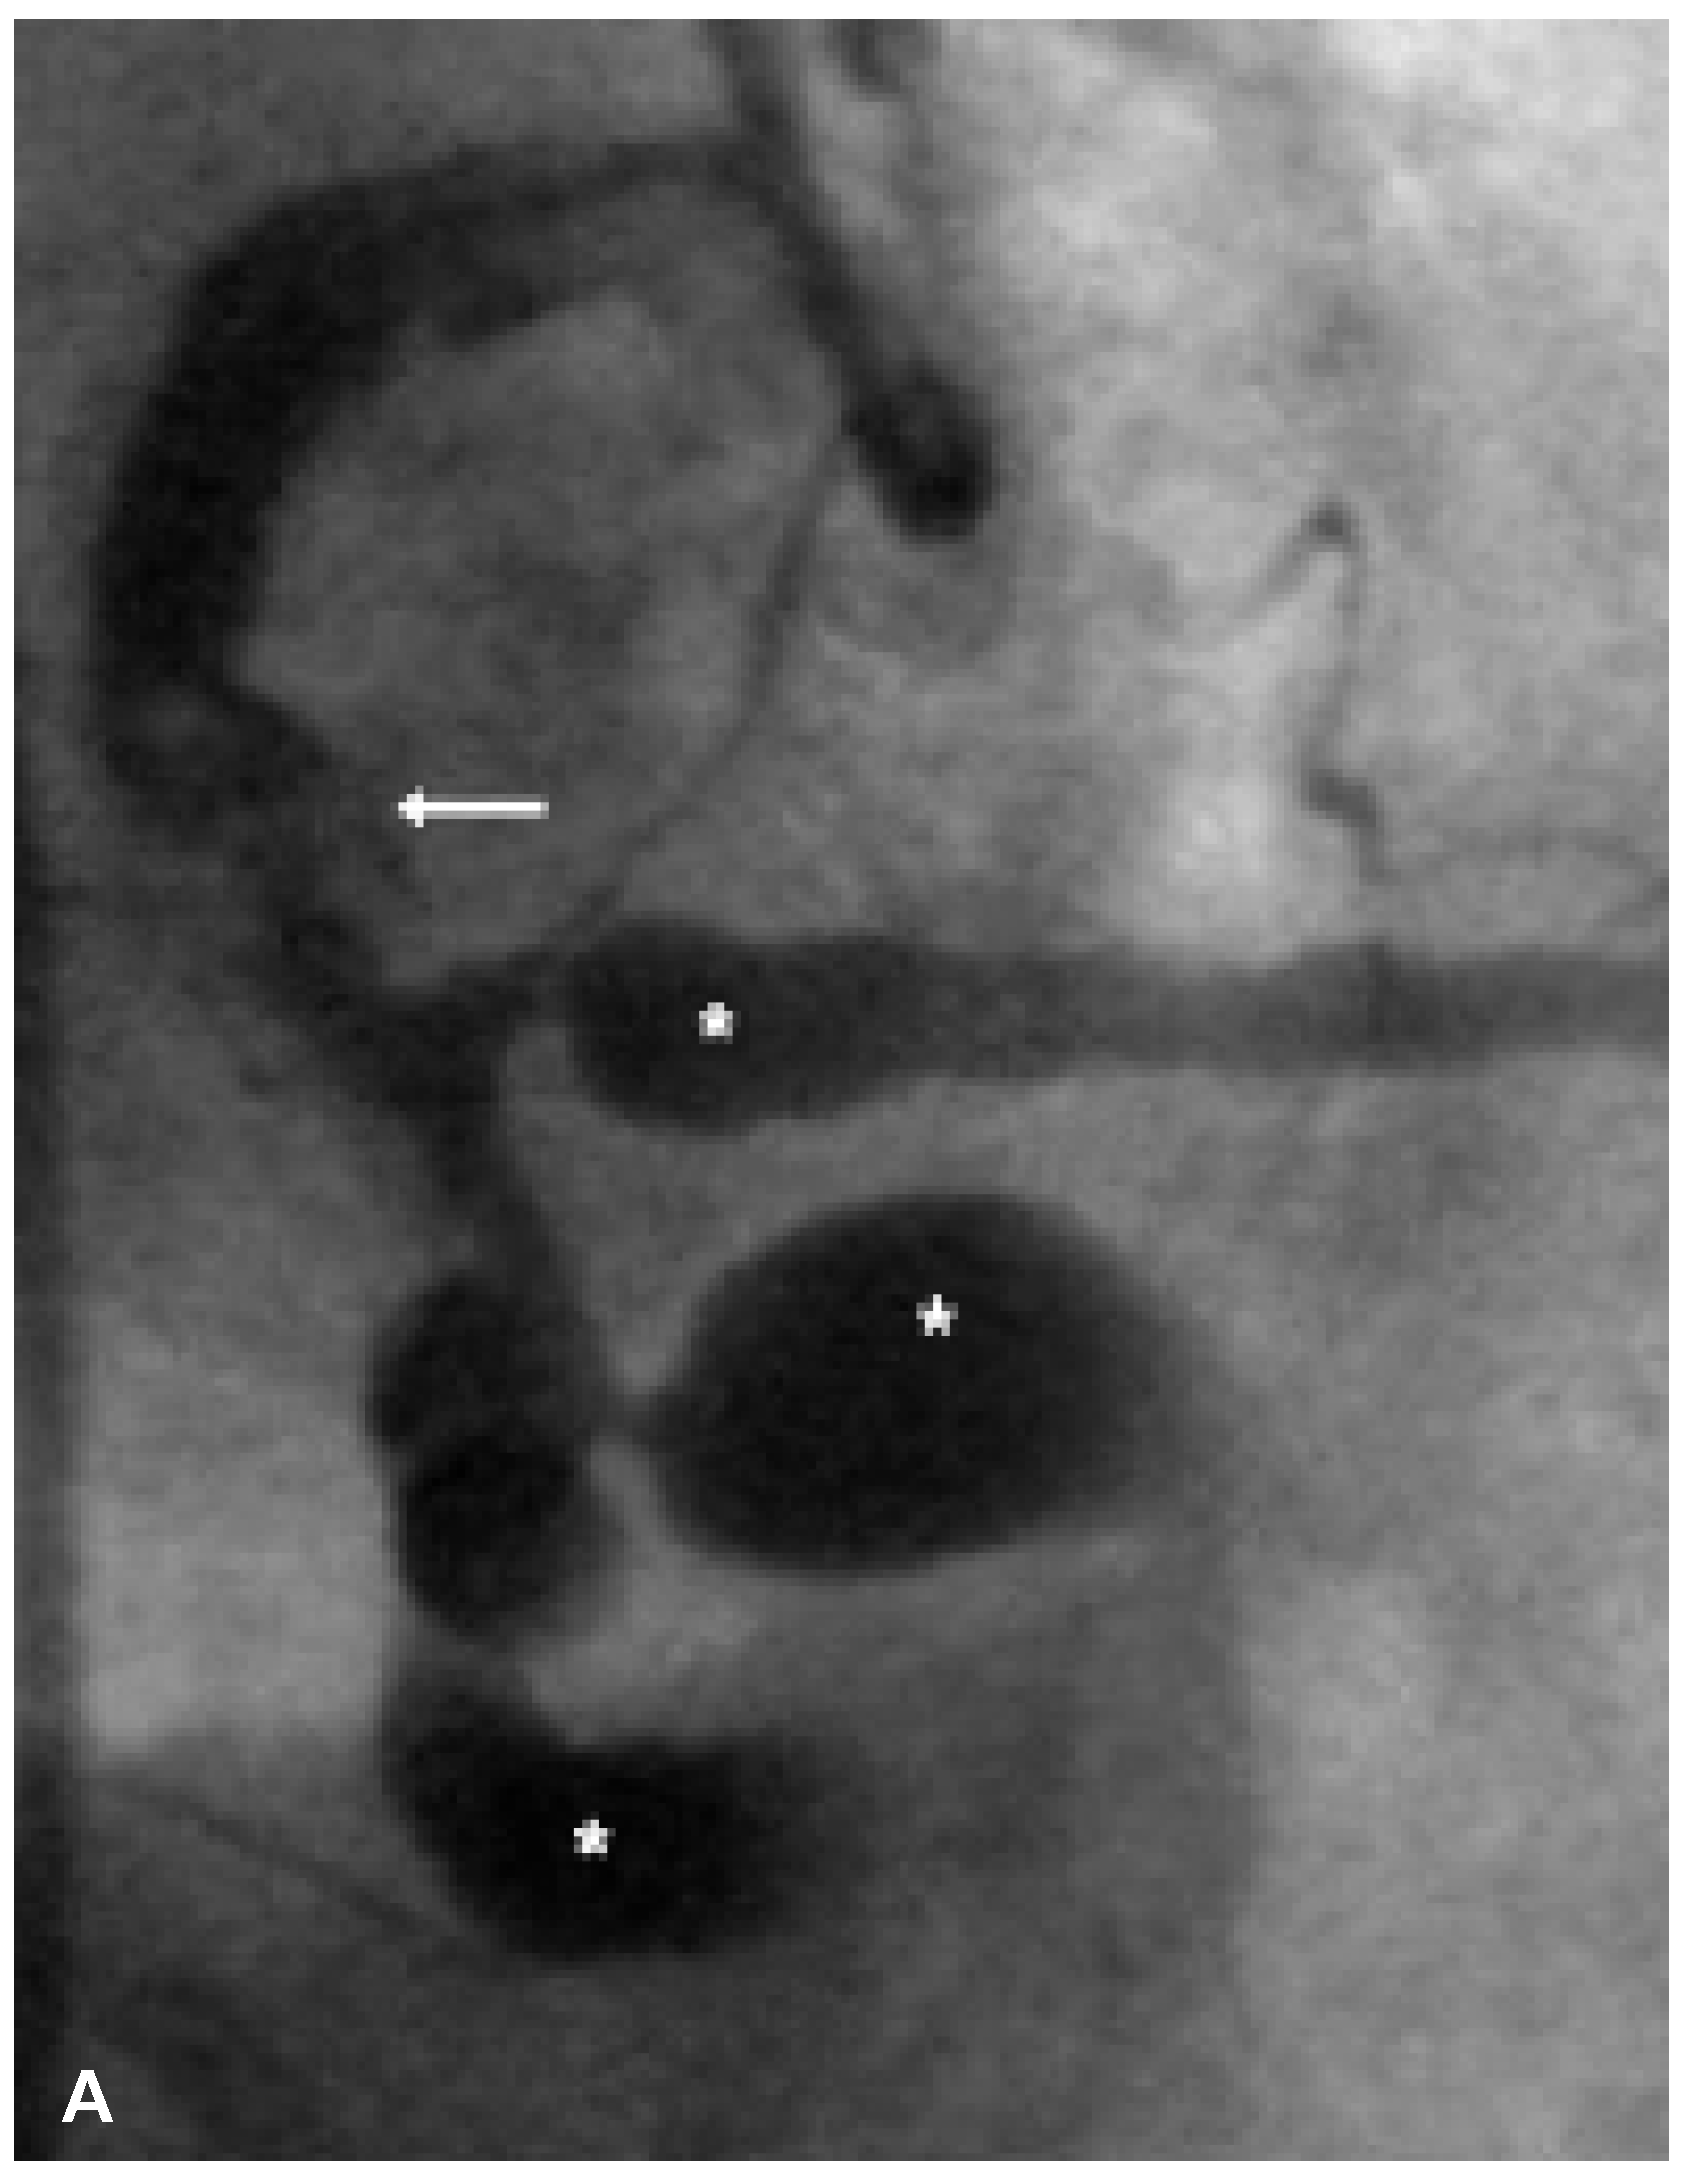

Severe Coronary Artery Ectasia and Abdominal Aortic Aneurysm

Case Report